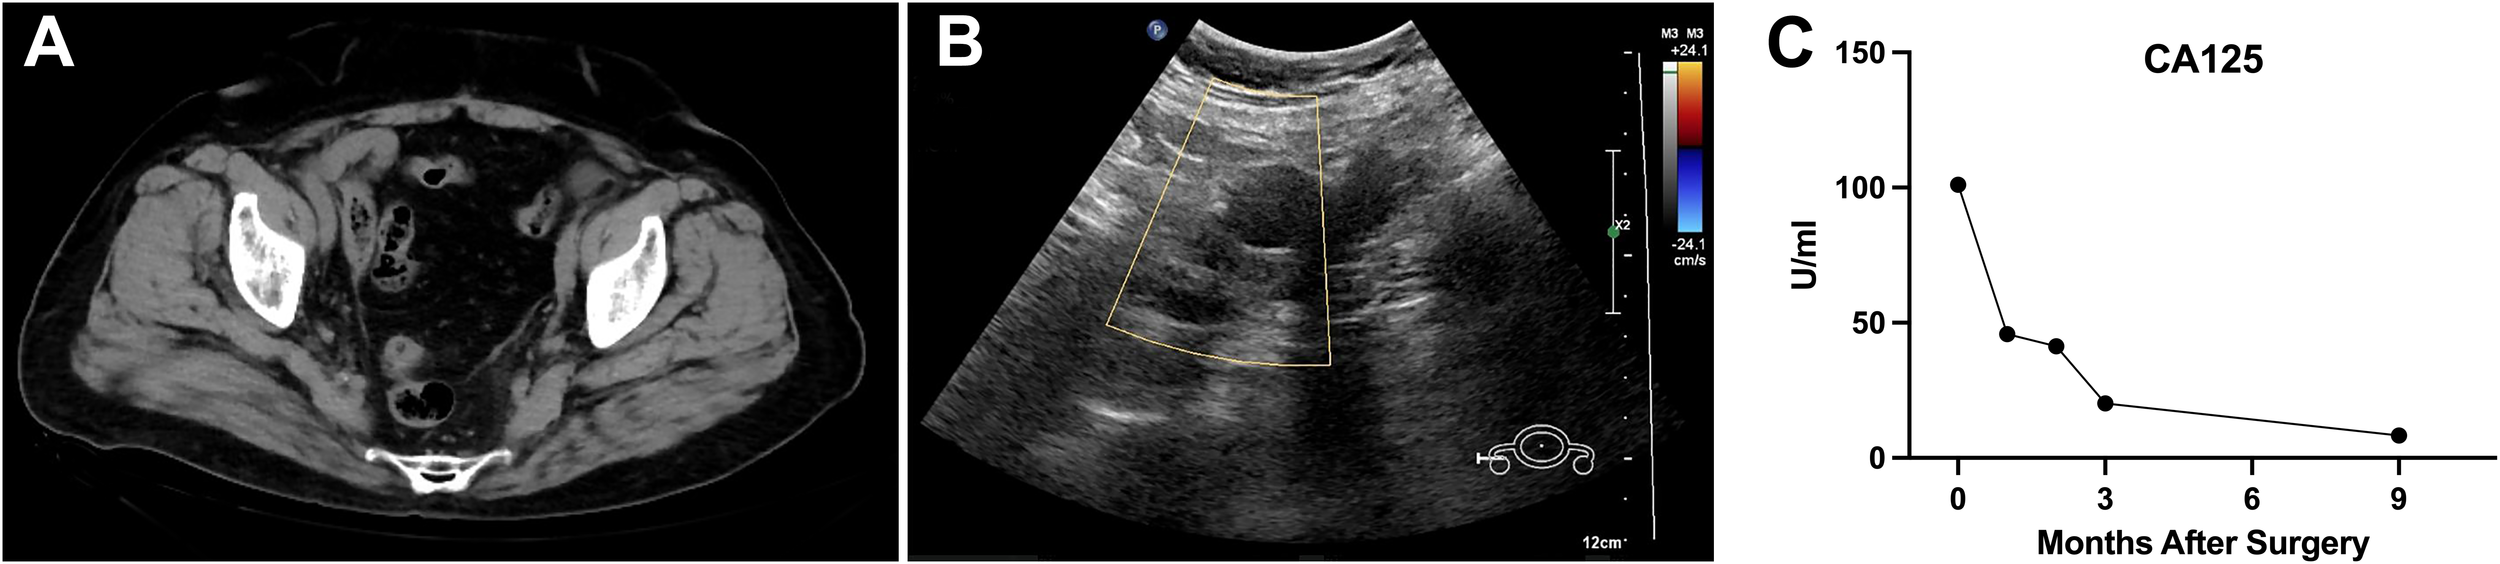

Postoperative pathology revealed a poorly differentiated malignant tumor in the left adnexa (11 cm × 7 cm × 7 cm) with necrosis. Tumor cells were arranged in nests or trabeculae, exhibiting marked nuclear atypia and frequent mitotic figures (Figures 2A, B). Immunohistochemical analysis showed creatine kinase (CK) (+), estrogen receptor (ER) (+), GATA3 (−), Inhibin (−), Ki-67 (+), P16 (+), P53 (+, wild type), paired box 8 (Pax-8) (+), PMS2 (+), Progesterone receptor (PR) (++), SALL4 (−), synapsin (Syn) (+), Vimentin (focal +), and WT-1 (+), indicating an embryonic origin of the tumor (Figures 2C–P). Genetic testing confirmed a Breast cancer type 1 (BRCA1) systemic mutation with established clinical significance and a TP53 mutation with potential clinical relevance. The patient was diagnosed with Wolffian adnexal tumor (International Federation of Gynecology and Obstetrics (FIGO) stage IC) and underwent four cycles of adjuvant chemotherapy with paclitaxel and carboplatin (TC regimen). The patient has been regularly followed up post-treatment. At 9 months after surgery, pelvic CT and gynecological ultrasound revealed no signs of recurrence or metastasis (Figures 3A, B). Additionally, serial tumor marker assessments demonstrated a sustained decline in CA125 levels (Figure 3C).

Figure 3

Postoperative follow-up imaging and tumor marker trends indicating no recurrence or metastasis. (A, B) Postoperative follow-up pelvic CT and gynecological ultrasound performed 9 months after surgery revealed no signs of recurrence or metastasis in the pelvic region. (C) Serial measurements of the tumor marker CA125 demonstrated a continuous downward trend post-surgery. CA125, cancer antigen 125.

The diagnostic accuracy for malignant WAT is reported to be as low as 17% (22). Histopathological features indicative of malignancy include intratumoral necrosis, capsular invasion, high mitotic activity, and marked cellular atypia (8). Malignant WAT has an estimated recurrence rate of 11%, with a median interval of 48 months, primarily affecting the lungs and liver (22, 23). Given the rarity of malignant WAT and the limited prognostic value of morphological and immunohistochemical markers, long-term follow-up is essential, yet no standardized treatment guidelines exist (24). Existing case reports often extrapolate treatment strategies from malignancies of similar anatomical origin. Prognosis is primarily determined by clinicopathologic staging, cellular atypia, and proliferation indices (3). Complete surgical resection, including hysterectomy, bilateral adnexectomy, and cytoreductive surgery, remains the preferred primary treatment for malignant WAT (6). In the present case, due to the poorly differentiated nature of the tumor, systematic lymphadenectomy was performed despite the absence of intraoperative evidence of lymph node involvement. This approach ensured accurate staging and ruled out microscopic nodal metastases, aligning with oncological principles for malignancies with uncertain biological behavior. The role of chemotherapy and radiotherapy remains controversial. Subsequently, the patient received four cycles of paclitaxel and carboplatin (TC regimen). Regular follow-up post-treatment revealed no evidence of recurrence or metastasis at 9 months, as confirmed by pelvic CT and gynecological ultrasound (Figures 3A, B). Additionally, serial CA125 measurements demonstrated a continuous decline post-surgery, further supporting the absence of residual or recurrent disease (Figure 3C). Long-term follow-up should be conducted to continuously monitor disease status, allowing for the timely detection and management of any recurrence or metastasis.